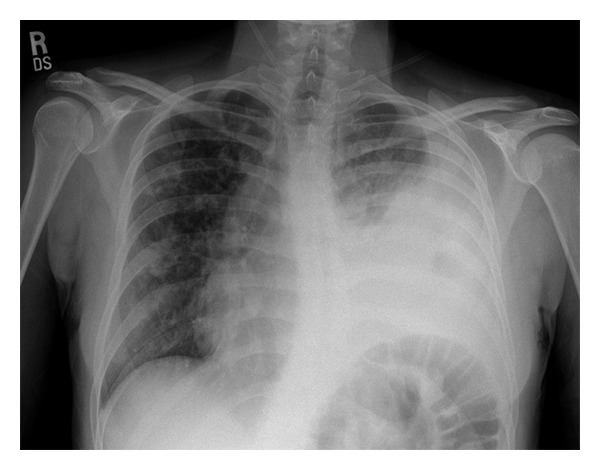

Input 2: What is seen in the X-ray and what should be done? ![]()